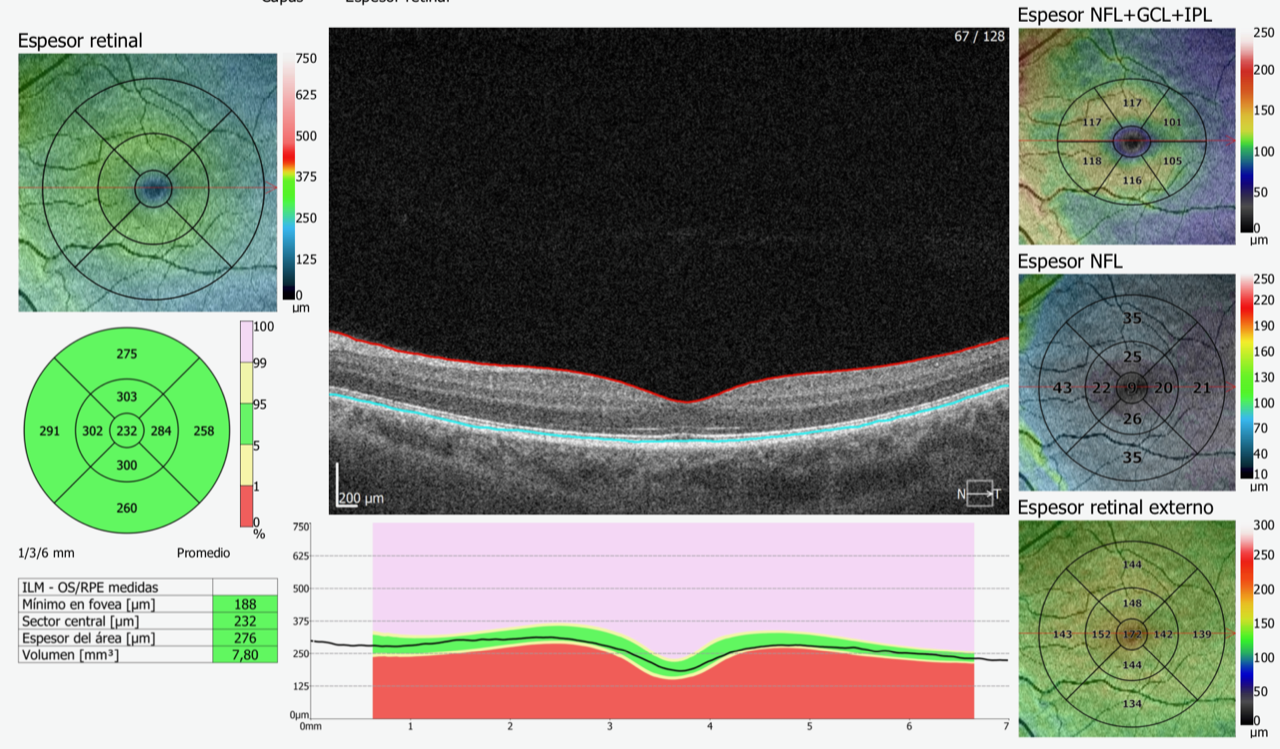

Oct

Estudio de la retina (principalmente la mácula) o nervio óptico mediante el cual un láser lee la superficie retinal y hace cortes ópticos de la misma que posibilita el examen de las diferentes capas de la misma. Nos Brinda mucha información sobre la micro estructura de la retina. Es de rápida obtención, inocuo y altamente reproducible. En muchos casos se complementa con estudios de angiografía digital o rfg.